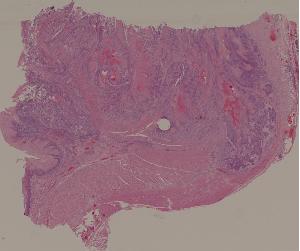

29.结肠腺癌